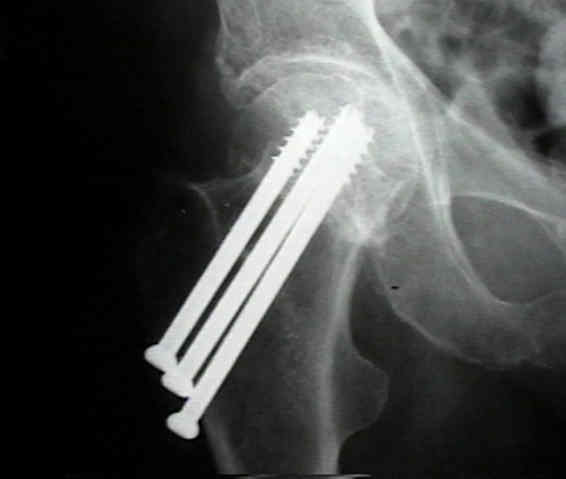

Trauma implant Cannulated Screw orthopedic implant,Cannulated Titanium Alloy Bone locking Screws,Medical Bone Screws

Durable 4.0 Mm Cannulated Screw Corrosion Resistant 20 - 68 Mm Length Images |